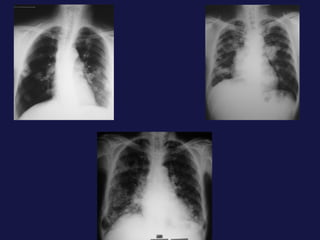

Metástasis al pulmón. El pulmón y el hígado son los mas FREC. Pueden tener varios tamaños. Imágenes nodulares, únicas o múltiples. Pueden cavitarse y calcificación.

Metástasis al pulmón.El pulmón y el hígado son los mas FREC. Pueden tener varios tamaños. Imágenes nodulares, únicas o múltiples. Pueden cavitarse y calcificación.